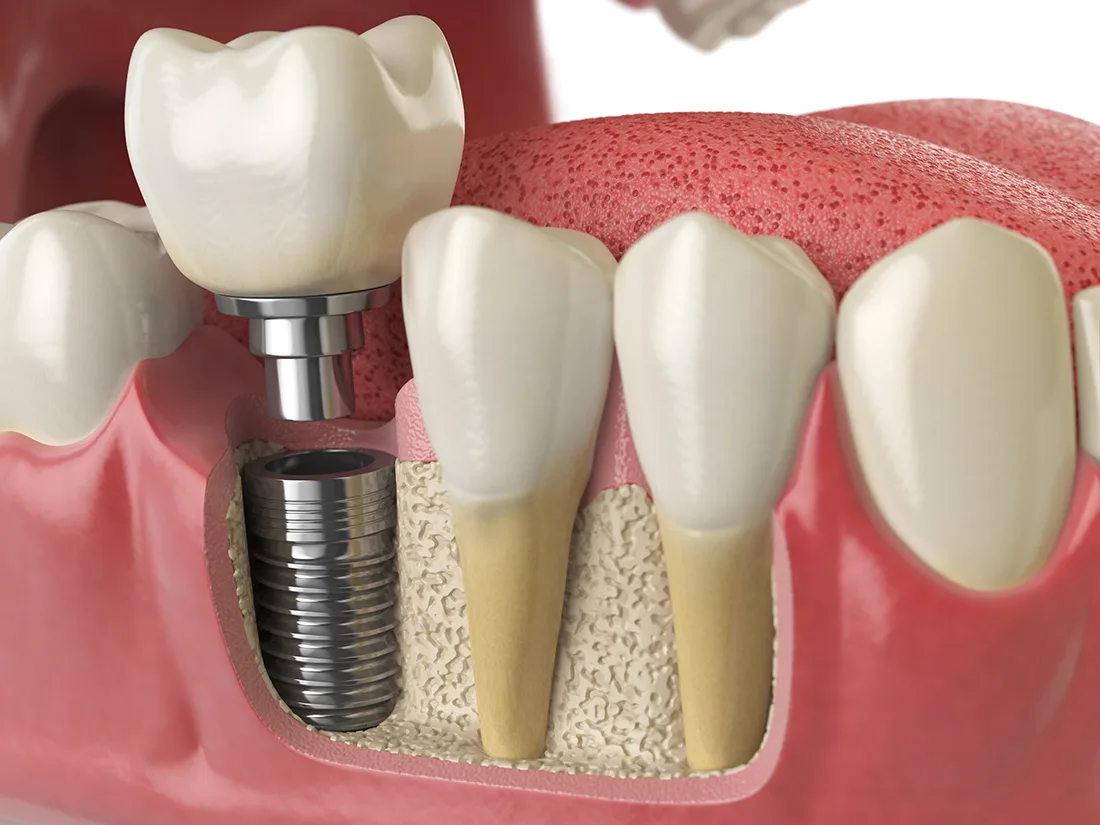

Dental Implants

Dental implants are a long-lasting and natural-looking solution for replacing missing teeth. They are surgically placed into your jawbone, acting as a strong foundation for a permanent tooth replacement, which restores both function and aesthetics.